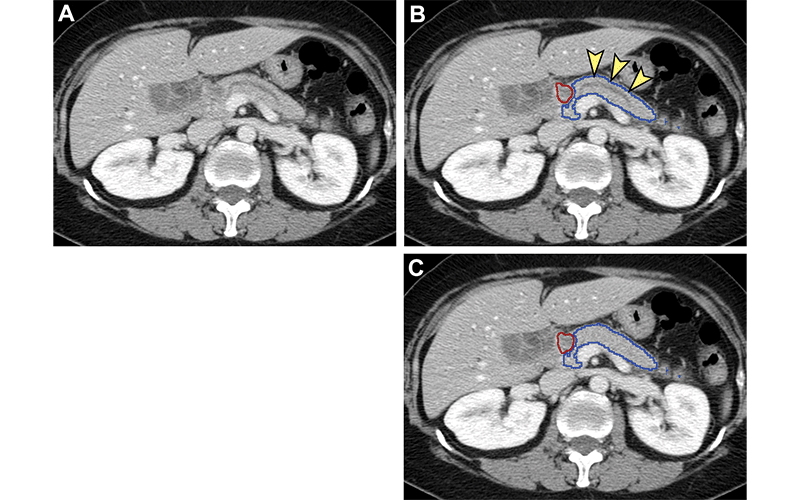

Analysis of nontumorous portion of pancreas with or without secondary signs of pancreatic cancer by classification models. Blue outline represents the portion of the pancreas analyzed with classification models. The tumor (red outline) was not identified by the segmentation model; thus, it was not analyzed by classification models. (A) Unannotated CT image in a patient with pancreatic head cancer. (B) Nontumorous portion of the pancreas shows secondary signs of pancreatic cancer (dilation of pancreatic duct with abrupt cutoff [arrowheads]) and was classified as cancerous by the classification models. (C) Nontumorous portion of the pancreas appeared normal and was classified as noncancerous after the dilated duct was replaced and imputed with surrounding normal-appearing pancreas parenchyma. https://doi.org/10.1148/radiol.220152 © RSNA 2022